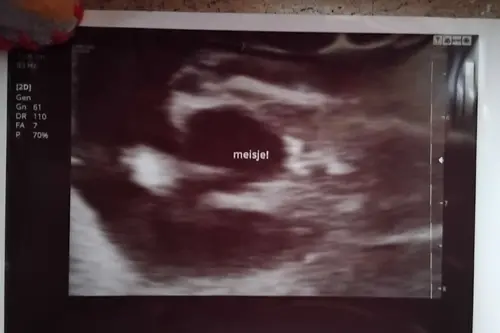

Ik had met 13+2 al een geslachtecho, volgens de echoscopist is het al betrouwbaar. Ik heb twee zoontjes en nu zwanger van een dochter! Ook nooit verwacht een dochter te krijgen.

Hier met 14+3. Ook zwanger van een dochtertje nadat ik 5 jaar geleden een dochtertje ben verloren en daarna 2 gezonde jongens heb gehad. Ik snap het gevoel van onwerkelijk.